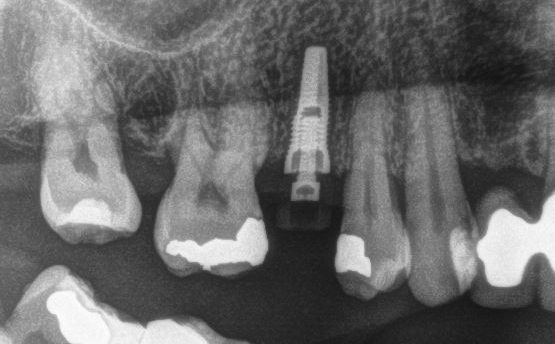

3D-Röntgen (DVT)

Import der CEREC-Planung in das 3D-Röntgenbild und Planung der exakten Implantatposition

Röntgenkontrolle

Nach der erfolgreichen OP wird die Position des Implantates röntgenologisch überprüft.